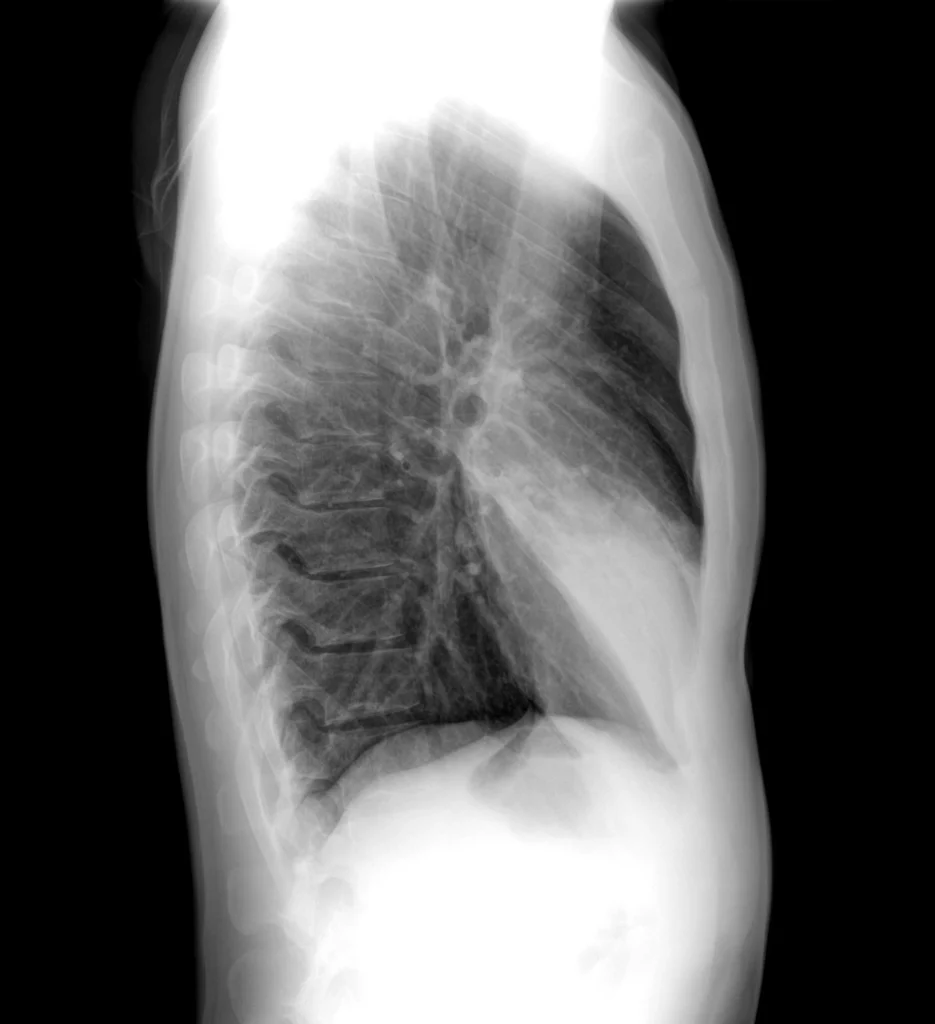

Rx de tórax lateral. La consolidación se proyecta sobre la silueta cardíaca, bien delimitada por las cisuras menor y mayor, confirmando la localización en el lóbulo medio.

En la proyección PA, se observa una consolidación en el tercio inferior del pulmón derecho, que borra el contorno del corazón, el signo de silueta es positivo. En la proyección lateral se confirma la localización de la consolidación en el lóbulo medio, proyectada sobre la silueta cardíaca.